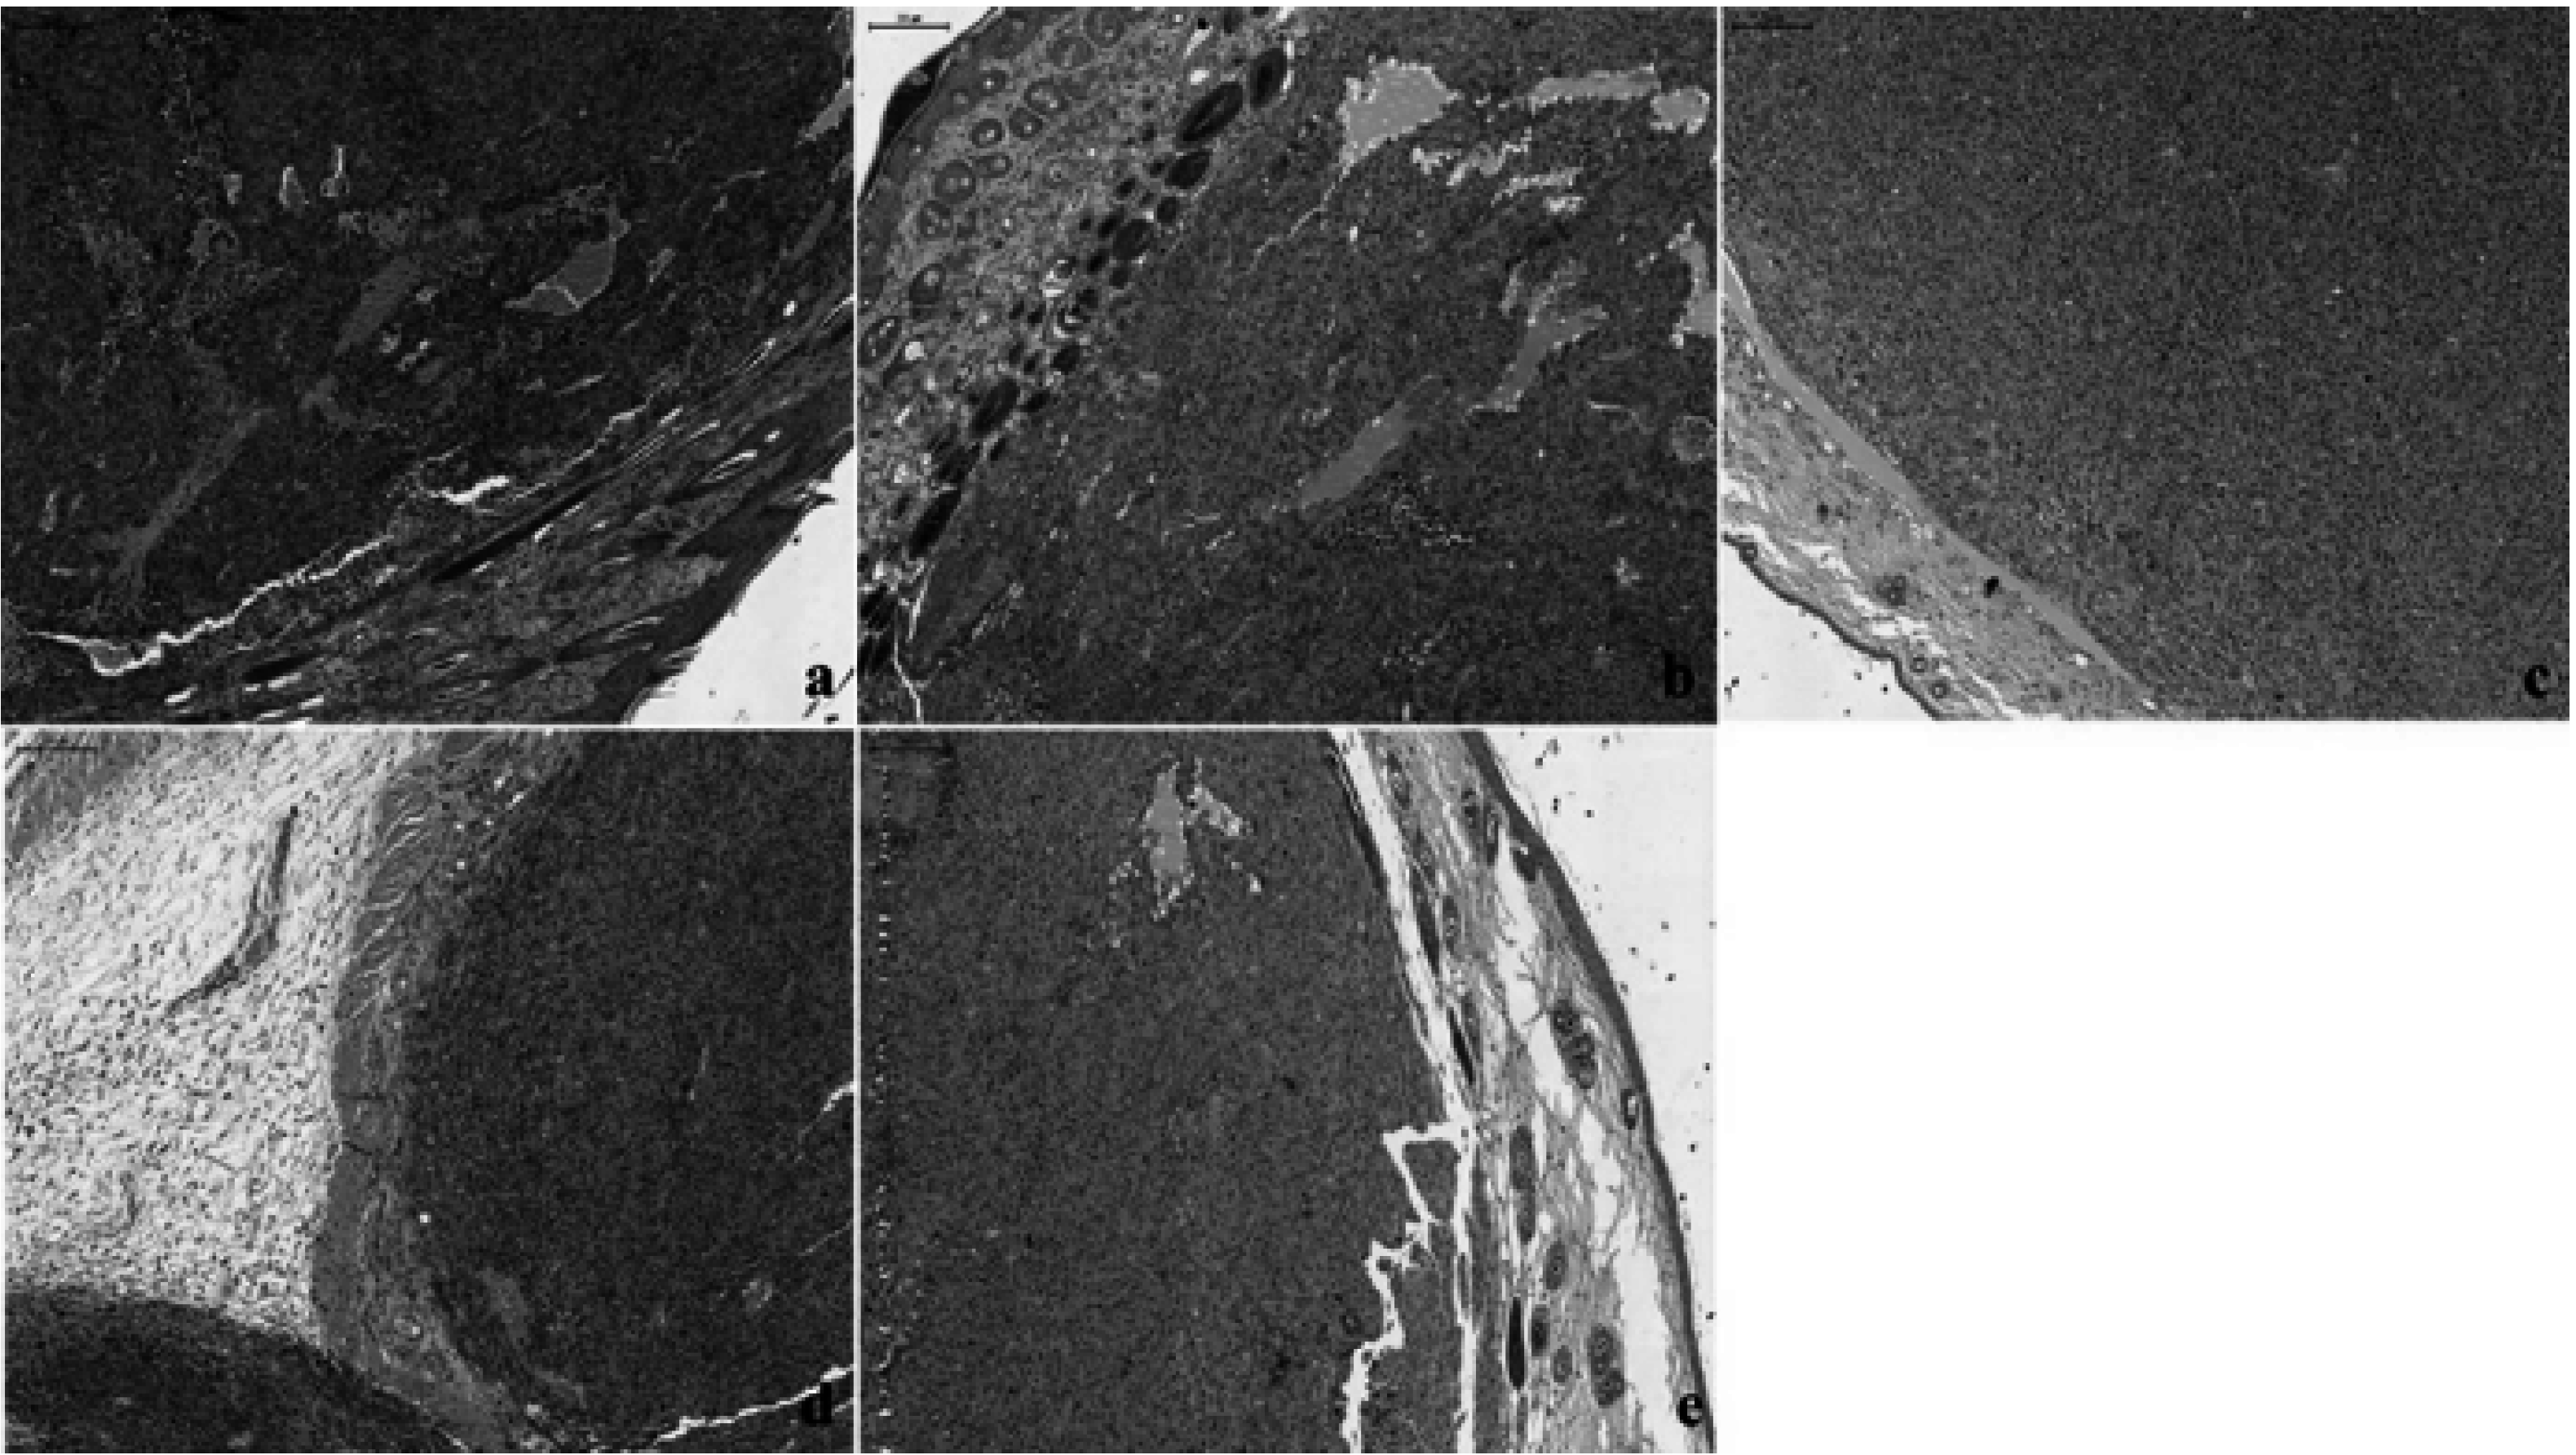

Conventional hematoxylin–eosin (HE) analysis revealed similar features in groups B and C, with moderate to intense pigmentation in almost all the tumor cells (Figure 8a,b). In group D, weak pigmentation was observed in isolated cells (Figure 8c). Group E was characterized by moderate pigmentation with intense pigmentation in a few nests of tumor melanocytes (Figure 8d). Group F exhibited similarities with group D, with a general feature of a lower level of pigmentation and with melanin present in a few tumor cells (Figure 8e).

Figure 8.

Hematoxylin–eosin (HE) staining in the different groups with skin melanoma: (a,b): groups B and C with moderate to intense pigmentation in almost all the tumor cells; (c): group D, exhibiting melanoma with weak and isolated pigment; (d): group E, displaying moderate pigmentation, with intense pigmentation in a few nests of tumor melanocytes; (e): group F, with the presence of melanin in isolated cells. Magnification: 40×; scale bar: 200 μm.